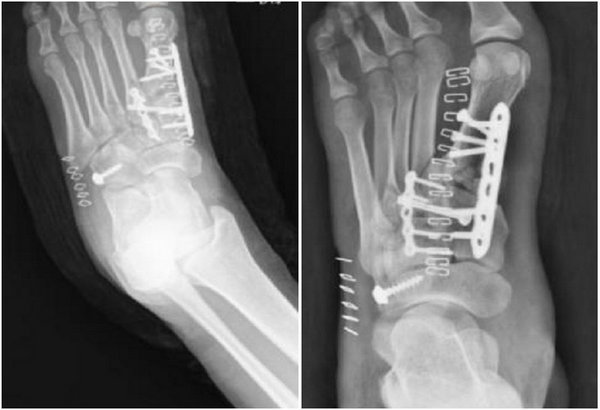

Lisfranc损伤的内固定植入物有多种选择,该病例同时存在骨折及脱位且关节面碎裂程度较重,重建难度大。李烁团队对该病例进行了充分的术前讨论并制定手术方案:给予左足第一跖骨及跖楔关节、第二跖骨及跖楔关节锁定钢板固定;同时给予Lisfranc螺钉固定以维持内侧楔骨和第二跖骨的稳定性;骰骨给予螺钉固定。经过周密的术前准备,李烁团队与手术室、麻醉科通力合作,顺利的为患者实施了手术。术后查体及影像学检查显示:患者骨折复位及固定效果良好。

术后影像